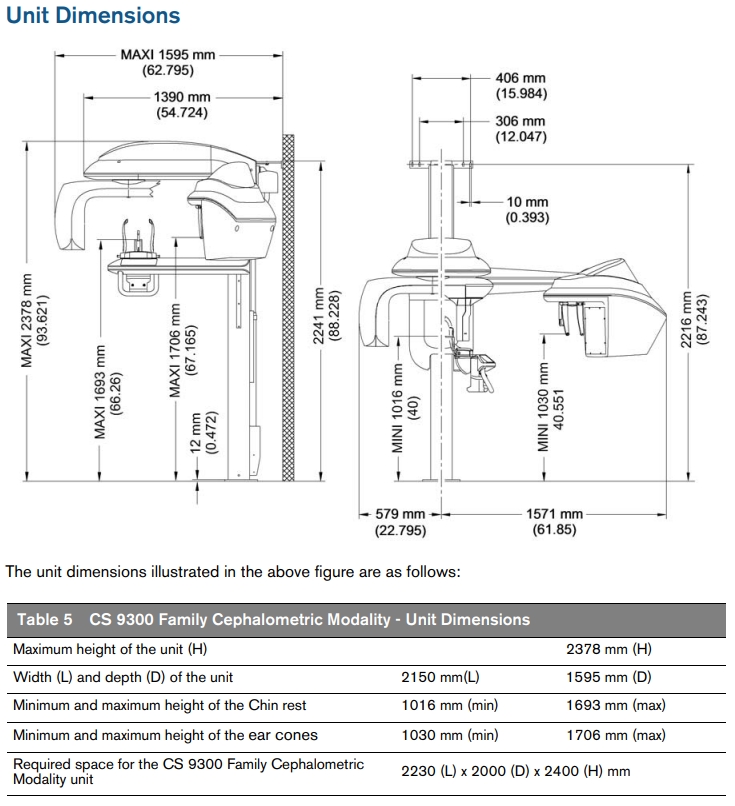

ACTUAL DIMENSIONS: 85"(W) x 63"(D)

RECOMMENDED DIMENSIONS: 88"(W) x 79"(D)